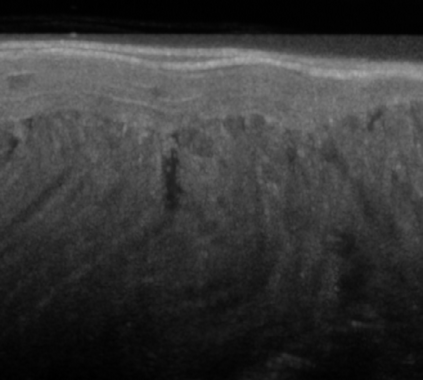

The statistical supervised learning framework assumes an input-output set with a joint probability distribution that is reliably represented by the training dataset. The learner is then required to output a prediction rule learned from the training dataset's input-output pairs. In this work, we provide meaningful insights into the asymptotic equipartition property (AEP) \citep{Shannon:1948} in the context of machine learning, and illuminate some of its potential ramifications for few-shot learning. We provide theoretical guarantees for reliable learning under the information-theoretic AEP, and for the generalization error with respect to the sample size. We then focus on a highly efficient recurrent neural net (RNN) framework and propose a reduced-entropy algorithm for few-shot learning. We also propose a mathematical intuition for the RNN as an approximation of a sparse coding solver. We verify the applicability, robustness, and computational efficiency of the proposed approach with image deblurring and optical coherence tomography (OCT) speckle suppression. Our experimental results demonstrate significant potential for improving learning models' sample efficiency, generalization, and time complexity, that can therefore be leveraged for practical real-time applications.